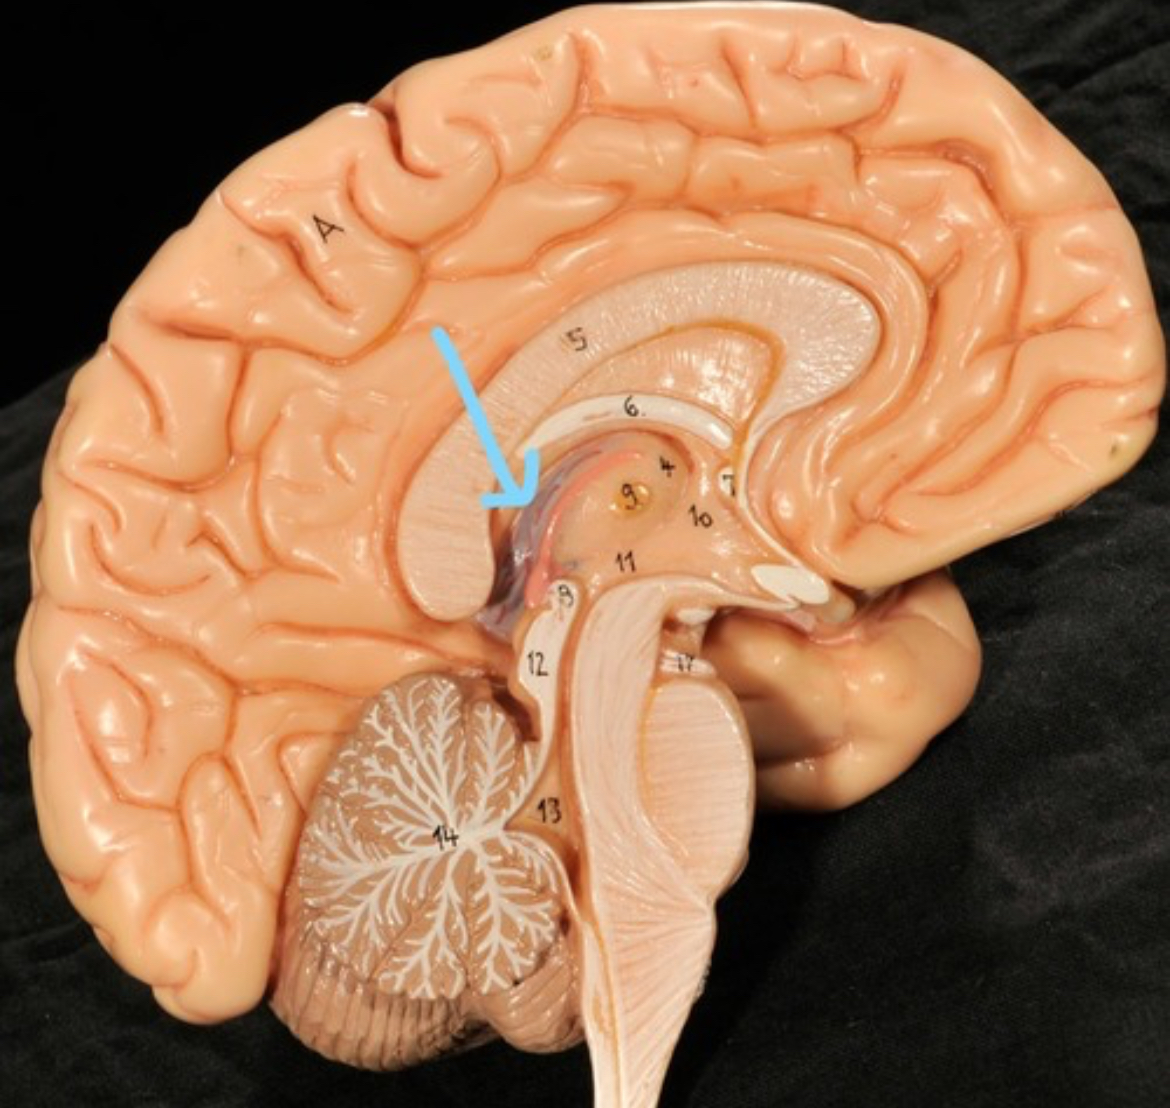

Corpus callosum

Diencephalon

Thalamus

3rd ventricle

Hypothalamus

Epithalamus (pink line)

Brain stem

Pons

Medulla oblongata

Choroid plexus of 3rd ventricle

Cerebral aqueduct (midrain)

4th ventricle

central canal